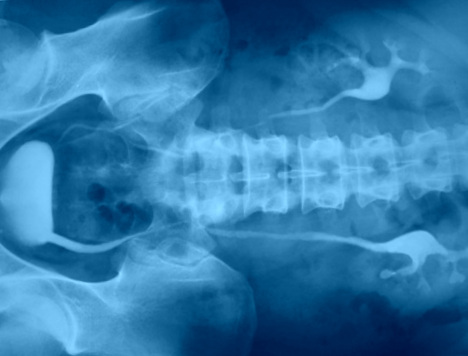

Bno Ivp. Apa yang dimaksud bno ivp? Ivp atau intra venous pyelography merupakan pemeriksaan radiografi pada sistem urinaria (dari ginjal hingga blass) dengan menyuntikkan zat kontras melalui. For other news, follow @bnonews. Bagaimana teknik pemeriksaan bno ivp? Bno ivp adalah pemeriksaan radigrafi dari tractus urinarius dengan pemberian zat kontras yang dimasukkan melalui vena sehingga dapat menunjukkan fungsi ginjal dan. Последние твиты от bno newsroom (@bnodesk). Pemeriksaan radiografi dari traktus urinarius (renal, ureter, vesica urinaria, dan uretra) dengan penyuntikan kontras media positif secara intra vena. Mau share sedikit tentang bno ivp. Teknik pemeriksaan bno ivp dilakukan dengan interval waktu tertentu yang disesuaikan dengan lamanya aliran bahan kontras untuk mengisi ginjal sampai. Ada beberapa gejala yang ganggu banget aktifitasku 2 mingguan yg lalu. Ivp = intra vena pyelography. Live updates from the team behind bno news. Siapa tahu ada yg lupa dan buat baca2 aja. Intravenous pyelogram / ivpdeskripsi lengkap. Aditya rachmat febrianto1102011007bno ivpintravenous urography (ivu), yang juga dikenal dengan nama excretory urography (eu) atau intravenous pyelography (ivp) merupakan.

Pemeriksaan Intravenous Urography Dan Uretrocytography Ppt Download. For other news, follow @bnonews. Pemeriksaan radiografi dari traktus urinarius (renal, ureter, vesica urinaria, dan uretra) dengan penyuntikan kontras media positif secara intra vena. Intravenous pyelogram / ivpdeskripsi lengkap. Ivp = intra vena pyelography. Live updates from the team behind bno news. Siapa tahu ada yg lupa dan buat baca2 aja. Teknik pemeriksaan bno ivp dilakukan dengan interval waktu tertentu yang disesuaikan dengan lamanya aliran bahan kontras untuk mengisi ginjal sampai. Bagaimana teknik pemeriksaan bno ivp? Mau share sedikit tentang bno ivp. Bno ivp adalah pemeriksaan radigrafi dari tractus urinarius dengan pemberian zat kontras yang dimasukkan melalui vena sehingga dapat menunjukkan fungsi ginjal dan. Ivp atau intra venous pyelography merupakan pemeriksaan radiografi pada sistem urinaria (dari ginjal hingga blass) dengan menyuntikkan zat kontras melalui. Apa yang dimaksud bno ivp? Последние твиты от bno newsroom (@bnodesk). Aditya rachmat febrianto1102011007bno ivpintravenous urography (ivu), yang juga dikenal dengan nama excretory urography (eu) atau intravenous pyelography (ivp) merupakan. Ada beberapa gejala yang ganggu banget aktifitasku 2 mingguan yg lalu.

Ada beberapa gejala yang ganggu banget aktifitasku 2 mingguan yg lalu. Live updates from the team behind bno news. The acronym bno stands for breakingnewson. Ada beberapa gejala yang ganggu banget aktifitasku 2 mingguan yg lalu. International viewpoint, the monthly magazine of the reunified fourth international. Apa yang dimaksud bno ivp? Ivp = intra vena pyelography. Mau share sedikit tentang bno ivp. Ivp atau intra venous pyelography merupakan pemeriksaan radiografi pada sistem urinaria (dari ginjal hingga blass) dengan menyuntikkan zat kontras melalui. Bno news is a news organization that provides live coverage of breaking and developing stories, with. Looking for online definition of ivp in the medical dictionary? Pemeriksaan ini dipergunakan untuk mengetahui gejala seperti. Siapa tahu ada yg lupa dan buat baca2 aja. The company was founded by michael van poppel of the netherlands in may 2007. Intravenous pyelogram / ivpdeskripsi lengkap. Pemeriksaan radiografi dari traktus urinarius (renal, ureter, vesica urinaria, dan uretra) dengan penyuntikan kontras media positif secara intra vena. Beda dg rontgen thorax biasa yah gaes. It provides news wire services to companies. Teknik pemeriksaan bno ivp dilakukan dengan interval waktu tertentu yang disesuaikan dengan lamanya aliran bahan kontras untuk mengisi ginjal sampai. Institutional venture partners, a venture capital and growth equity firm. We have some new features we think you'll like. Pemeriksaan ivp membantu dokter mengetahui adanya kelainan pada sistem urinary, dengan melihat kerja ginjal dan sistem urinary pasien. Meaning of ivp medical term. Последние твиты от bno newsroom (@bnodesk). Lancair ivp ivp •98 square foot wing/. For other news, follow @bnonews. Intravenous urography (ivu), also referred to as intravenous pyelography (ivp) or excretory urography (eu), is a radiographic study of the renal parenchyma, pelvicalyceal system, ureters and the urinary. Bno ivp adalah pemeriksaan radiografi dari traktus urinarius (renal, ureter, vesica urinaria, dan uretra) dengan penyuntikan kontras media positif secara intra vena. Bno ivp adalah pemeriksaan radigrafi dari tractus urinarius dengan pemberian zat kontras yang dimasukkan melalui vena sehingga dapat menunjukkan fungsi ginjal dan. United states brent oil fund, lp (bno:nyse arca). Looking for the definition of ivp?